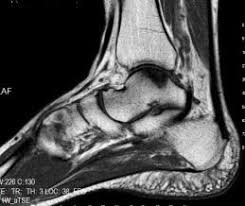

- 1.5 cm kareden dah büyük bir lezyonun MRG görüntüsü